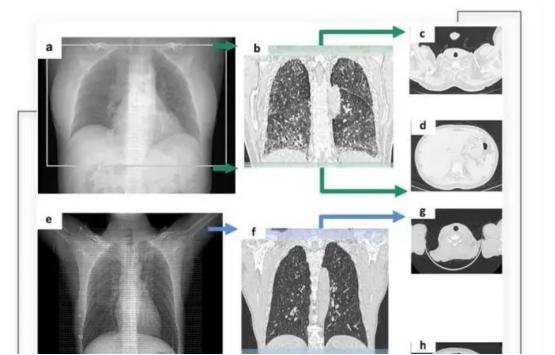

AI医学影像分析,则是利用机器学习、计算机视觉等技术,对医学影像数据进行自动化分析和诊断,并根据大量的定量特征,如形态、纹理、灰度、强度等,与基因、临床等其他数据进行关联分析,发现疾病的生物标志物和预后因素。

通过搭载了智能算法的CT摄像头,将深度学习卷积神经网络与典型的模式识别算法创新地结合在一起,从而精准识别CT扫描范围。

其主要技术,是通过深度学习及卷积神经网络模型,模仿人类认知过程,让AI模型自动挖掘医学图像中的规律。

其AI产品InferOperate,通过对脑电图、脑功能成像等多种类型的神经影像数据进行深度学习,提取影像特征,定位病灶,从而为医生提供智能手术规划、术中全自动定位导航等。